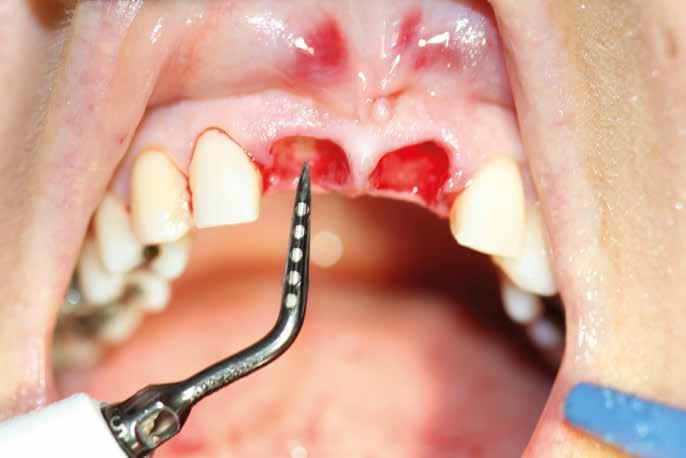

Deve prevedere sia l’osservazione sia la palpazione di tutte le mucose orali, partendo da labbra, lingua, guance, per arrivare alla valutazione del tessuto gengivale dei fornici, del palato e la gengiva aderente. Se ne devono valutare colore (fig. 11 ittero mucoso), fragilità, consistenza e presenza di ulcere o tumefazioni.

L’esame clinico rappresenta sicuramente la fase di analisi più complessa in quanto i parametri da valutare sono molti e possono interessare tutte le specialità odontoiatriche. Sono da valutare lo stato di salute della dentatura residua, la presenza o meno di manufatti protesici, il rapporto intermascellare,

lo stato di igiene orale, la condizione dei tessuti parodontali, le abrasioni dello smalto che ci indirizzino verso la diagnosi di parafunzioni come il bruxismo, la limitazione nell’apertura della bocca o la presenza di deviazioni per disordini temporo-mandibolari. (Figg. 16-21)

FIG. 17 FIG. 16 FIG. 19 FIG. 18 FIGG. 16-21: Valutazione FIG. 21 FIG. 20